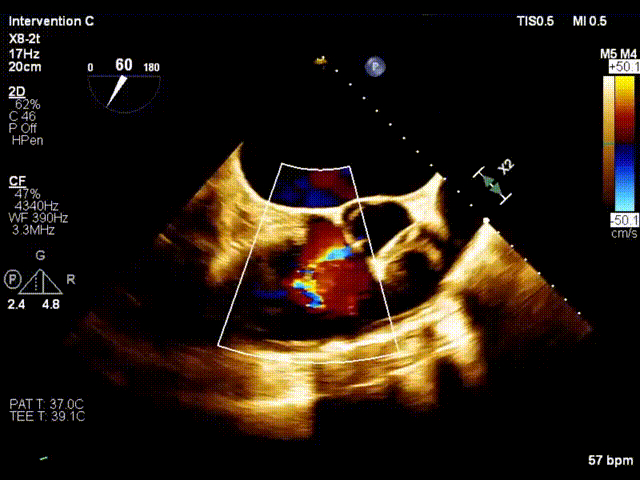

术前超声

术后超声